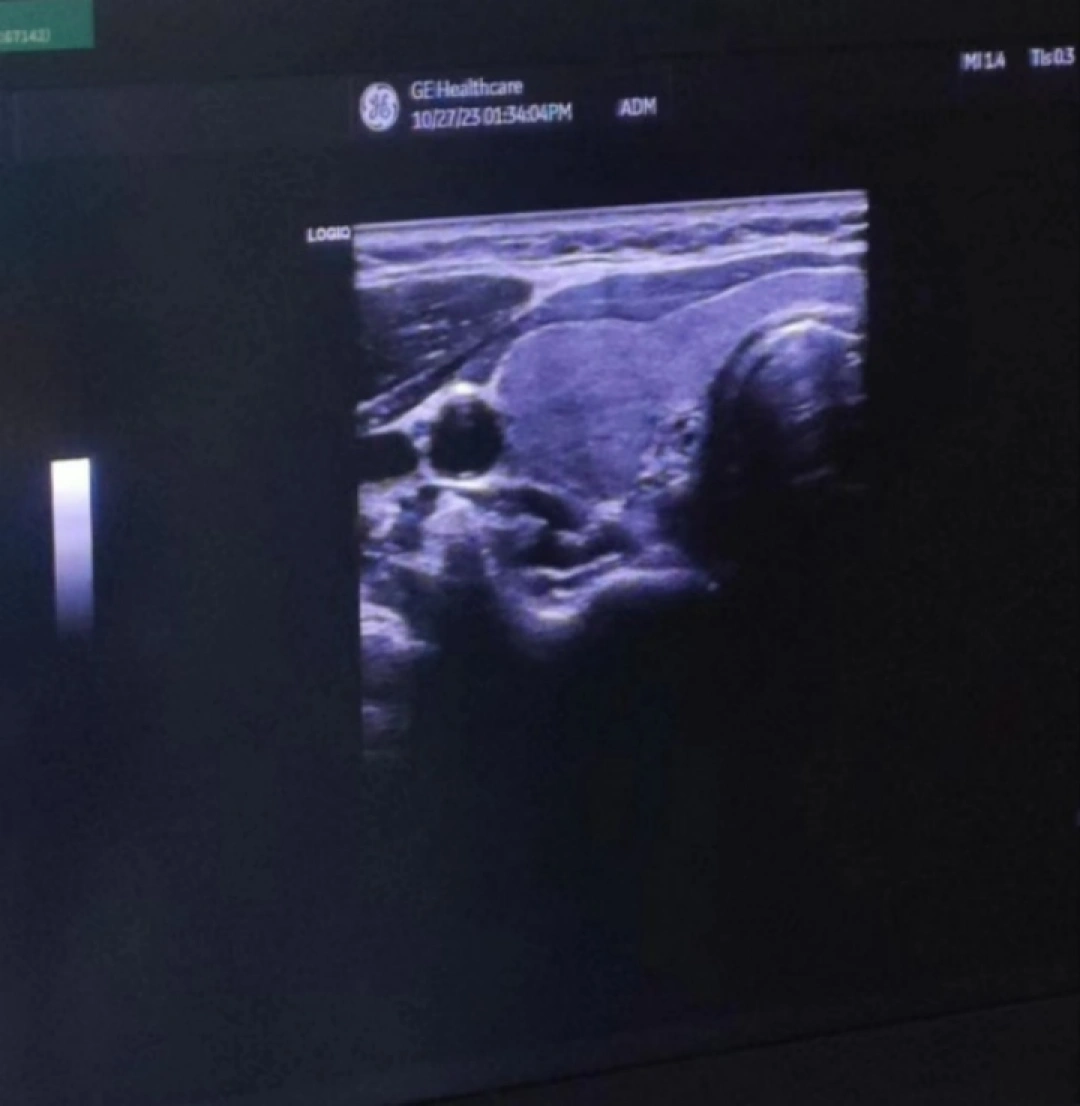

当天,手术在超声介入室进行。在局麻下借助彩超设备对病灶和治疗针具的精确显示和引导,将微波消融针穿刺到甲状腺病灶内,通过微波产生的高温,引起病灶组织发生局部凝固性坏死,整个手术过程耗时不到30分钟,术后超声造影进一步证实甲状腺结节血供消失,瘤体完全灭活。

△手术前和手术中超声影像对比。